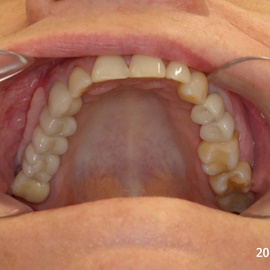

Bezzębie całkowite górne. Początkowo wykonane na mieście mosty całoceramiczne wydawały sie sukcesem, ale po roku pojawiły sie obrzęki i krwawienie z dziąseł. Pacjentka zgłosiła się do leczenia. Usunięto wszystkie zęby w szczęce. Sterowana regeneracja tkanek kości wyrostka, modelowanie kształtu i objętości tkanek miękkich, mosty porcelanowe przykręcane do implantów. Zadowalający wynik anatomiczny i estetyczny.